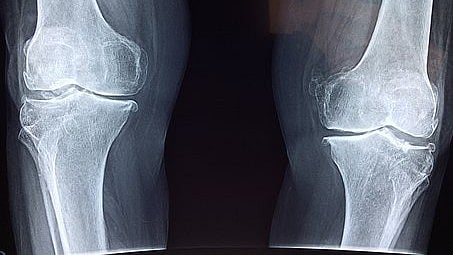

Osteoarthritis is a degenerative joint disease caused by the breakdown of cartilage that afflicts more than 35 million adults in the U.S. The exact mechanism of cartilage breakdown in osteoarthritis is unknown, but damage from mechanical stress with insufficient self-repair is believed to be the main culprit.